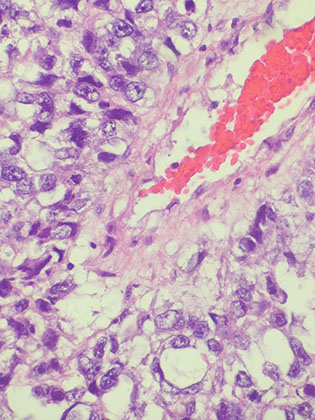

Granulomatous orchitis seen in middle-aged dudes c nut pain and possible fever

- nut looks big and nodular

Micro: granulomas restricted to seminiferous tubules